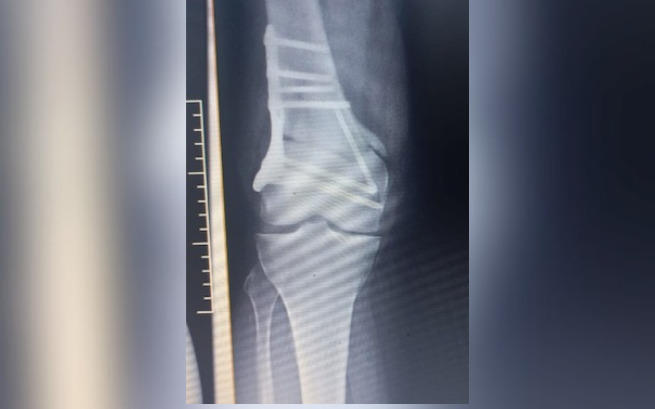

Przed nami kolejne leczenie, zabiegi, operacje, konsultacje ze specjalistami oraz dalsza diagnostyka. Ostatnia reoperacja (17.05.) odbyła się planowo. Po wcześniejszej operacji (22.03.) w dalszym ciągu pozostały poważne komplikacje w postaci braku zrostu w kości udowej. Co więcej, od strony zewnętrznej zespolenie zsunęło się, co konfliktuje z maziówką w wyniku czego ponownie wbijają się w nogę trzy gwoździe, powodując okropny ból.

Tak było kolejny raz z ostatnia operacją Patrycji (22.03), która niestety zakończyła się dużymi powikłaniami. W ich wyniku doszło do silnego zakażenia oraz pęknięcia kości udowej. Kiedy nasza przyjaciółka uporała się z zakażeniem, to okazało się, że kawałek ostrej śruby przedostał się poza kość i rani jej tkanki miękkie.

Dlatego dziś odbędzie się kolejna reoperacja. W wyniku tych okoliczności przedłuży się również okres rehabilitacji.

Obecnie Patrycja zmaga się z licznymi powikłaniami po operacji nogi wykonanej w ramach NFZ w sierpniu 2022 roku. Operacja z niewiadomych przyczyn - została wykonana tylko częściowo, niezgodnie z wcześniejszymi zaleceniami, wynikającymi ze skierowania. Po ostatniej konsultacji i diagnostyce okazało się, że noga ta wymaga natychmiastowej reoperacji oraz rekonstrukcji, aby można ją było uratować.